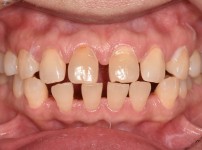

앞니 벌어짐

치아교정